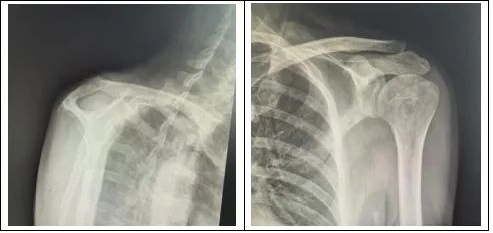

经过团队反复研讨,副主任医师李政为王先生实施了左肩关节松解术,肩袖锚钉缝合术,并在术中使用了双排锚钉。双排锚钉可以提供更强大的稳定性,可以使得肩关节在术后可以进行早期功能锻炼。该手术完美解决了治疗中的矛盾,整个手术过程不过两个小时。

王先生在术后很快感觉自己的肩膀轻松了,夜间睡觉也不会被疼醒了,困扰自己的问题终于得到了解决。在后续的康复锻炼中,王先生惊奇发现自己的胳膊可以正常抬起,疼痛也明显减轻了,并在不久的将来即可恢复正常的生活,对此他感到非常满意。